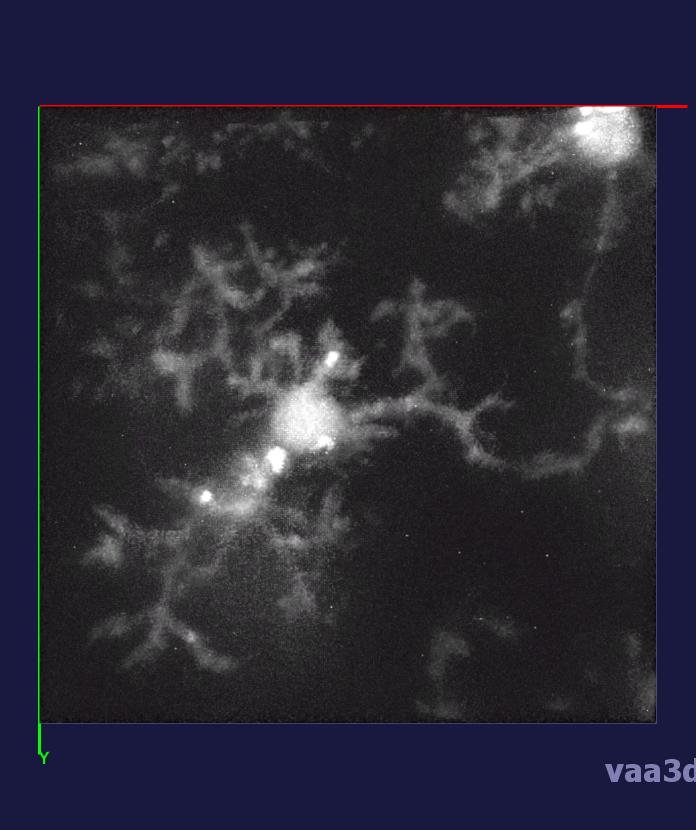

In our experiments, we compare the coupled TuFF-BFF microglia segmentation results with those given by L2S [21] and the Chan-Vese segmentation method [22]. The groundtruth in 3D was attained by manually tracing the object slice by slice from the z-stack. It must be noted that this was done by eye and could have some error. Figure 2 shows the visual comparison of the segmentation results for our dataset. Our result shown on the third column captures both the soma and processes. Figure 3 shows the Dice coefficient comparison of each segmentation method to the ground truth. Since the soma is much larger than the fine processes in the microglia, the processes have less volumetric impact on the similarity score. As explained in Section 1, segmenting the processes is important for quantifying the extension from the soma and its volume of surveillance. We use the Dice coefficient to quantitatively compare the ramification by taking the convex hull of the resulting segmentation. The Dice coefficient is a similarity measure that is computed using with where is the ground truth and is the compared image.

From Figure 4, the average Dice score for coupled TuFF-BFF was 0.77, compared to 0.53 for L2S [21] and .58 for Chan-Vese [22]. It must be noted that L2S required manual user initialization for each 2D image in the stack. While the Chan-Vese method has automatic seed selection, our coupled TuFF/BFF method was the only method that was a true 3D segmentation algorithm. L2S could not consistently capture the entire processes due to the intensity inhomogeneity throughout the object and background noise. The Chan-Vese segmentation could capture the extensions of the processes but did not work well with noise and attained false positives in the reconstruction. Since our method uses the tubular and blob information of the object to separate foreground and background, the segmentation only evolved within the object boundaries.